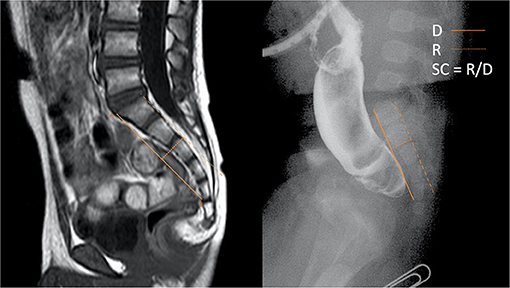

Figure 1. (A) The calculation of SR (6). (B) the measurement of SC.

The measurement of SC is illustrated in Figure 1B. A-point is the junction of the superior and the ventral margin of the first sacral vertebra on the lateral viewed image; B-point is the junction of the inferior and the ventral margin of the fifth, or the last sacral vertebra. D indicates the distance between A and B. R represents the vertical distance from the highest point on the dorsal curve of the sacrum bending to the AB line. SC is the ratio of R to D. SC is measured in the sagittal views of the MRI or the lateral radiograph of the sacrum (Figure 2). When the sacrum is dorsally curved, the AB line is drawn on the dorsal side of the sacrum. SC is presented as a negative value. A dorsally curved sacrum was defined as SC ≤ 0.